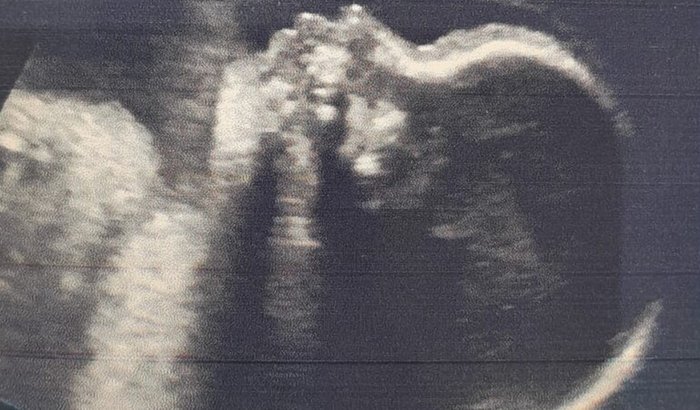

Estou criando essa vaquinha em prol de ajudar dois jovens Jefferson (meu primo e sua esposa sandy ) que terão seu primeiro bebê, estão com dificuldade financeira para comprar o enxoval, da nossa princesa Isabella que irá nascer no mês de setembro.